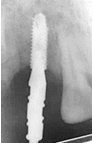

Cone beam examination revealed mesio distal space: 8mm , Bone thickness<6mm and Available bone height: 15mm (Figure 5)

Figure 5 Cone beam + sagittal sections.

The low bone volume represented a real surgical difficulty in placing a standard diameter implant.

4. The clinical and radiological results led us to a restoration with a narrow implant of 3.3 mm diameter, with a length of 11.5 mm.